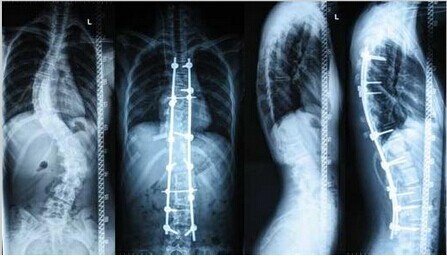

导读: 脊柱侧凸俗称脊柱侧弯。轻度的脊柱侧凸通常没有明显的不适,外观上也看不到明显的症状;较重的脊柱侧凸则会影响婴幼儿及青少年的生长发育,使其变形。轻度的脊柱侧凸可以观察,严重者需要手术治疗。

导读: 脊柱侧凸的矫正方式已经从单一平面和单一方向的矫正,发展到多平面和多节段的矫正,矫正效果也有明显提高。但由于脊柱侧凸本身的变化较大,分型较多,因而在手术治疗的方法选择时有较大的争议。